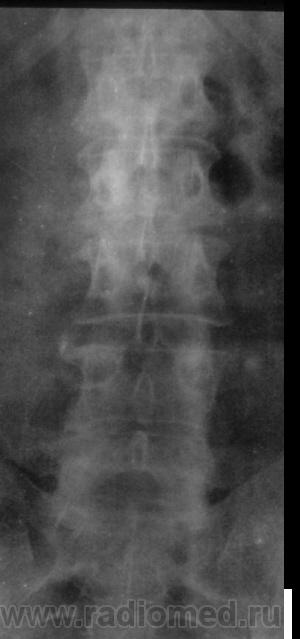

Пол пациента: Женский пол Тип патологии: Сосудистое заболевание Область исследования: Спинной мозг и периферическая нервная система Методы исследования: Rg Женщина поступила в неврологическое отделение с жалобами на онемение нижних конечностей. Сильные боли при повороте туловища, наклоне. https://radiomed.ru/sites/default/files/styles/case_slider_image/public/user/12/2.sl272924-1a.jpg?itok=gqeBvoQ7 ID:5809 Втр, 24/08/2010 - 17:32 #1 Катенёв Валенти... Не на сайте Был на сайте: 7 лет 2 недели назад Зарегистрирован: 22.03.2008 - 22:15 Публикации: 54876 На мой взгляд, при такой комбинации антелистозов, конечно, может быть, и не только "онемение" ног. Приложения: Ср, 25/08/2010 - 23:05 #2 Катенёв Валенти... Не на сайте Был на сайте: 7 лет 2 недели назад Зарегистрирован: 22.03.2008 - 22:15 Публикации: 54876 А. где пациент Игорь Артурович? Чт, 26/08/2010 - 00:25 #3 stroganoff Не на сайте Был на сайте: 15 лет 2 месяцев назад Зарегистрирован: 26.05.2010 - 16:53 Публикации: 57 А еще в Th12 есть крупный задний остеофит.

На мой взгляд, при такой комбинации антелистозов, конечно, может быть, и не только "онемение" ног.

А еще в Th12 есть крупный задний остеофит.